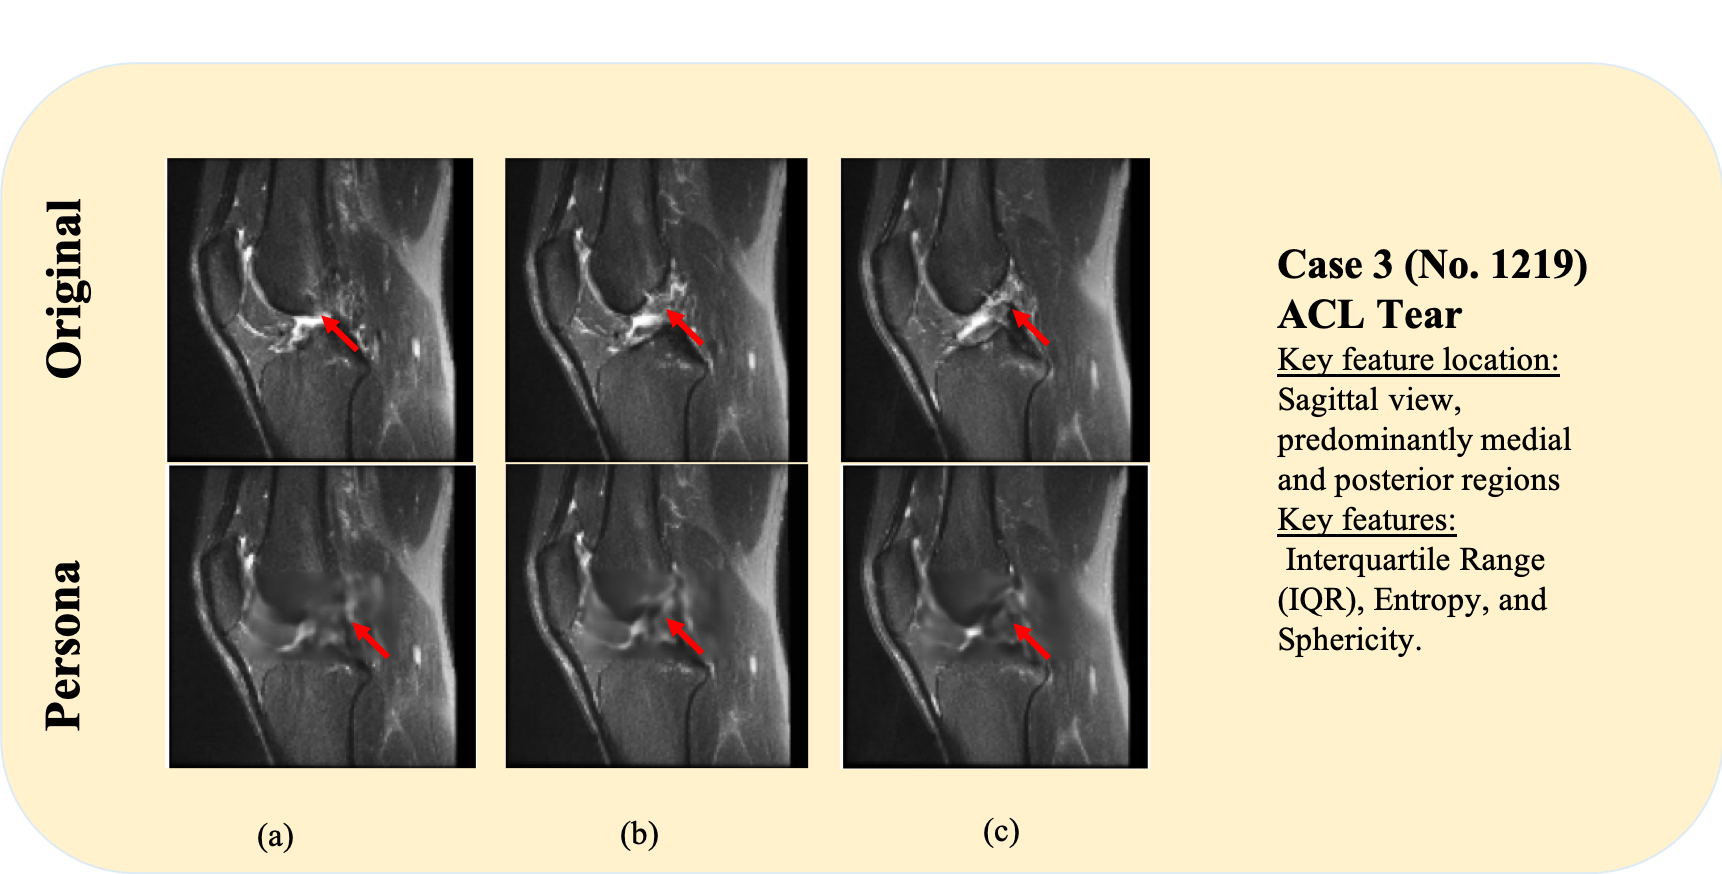

6.5 Case 3: ACL tear

This case presents an ACL rupture. The sagittal MRI plane is most suitable for evaluating ACL integrity. Fig. 6a– 6c display the original images, which show clear signs of ligamentous disruption (as indicated by the red arrow). These include fiber discontinuity, abnormal contour and periligamentous hyperintensity. In the corresponding persona images, the ACL appears more continuous and homogeneous in signal. Plus, compared with the original scans, the tibial translation is not clearly evident in the paired persona.

Radiomic feature analysis further supports the diagnosis. Key features in this case are localised primarily in the sagittal view, with dominant contributions from medial and posterior regions, consistent with the anatomical location of the ACL. Among the most informative features are IQR, Entropy and Sphericity. The IQR reflects tissue heterogeneity caused by partial fiber rupture. Entropy quantifies signal complexity and randomness, correlating with the structural disorganization observed in ligamentous injuries. Sphericity, a shape features, may relate to the deformation of the ACL’s normal linear morphology following rupture.

These cases highlight the role of personas in supporting visual interpretability. By providing a reference state, personas can assist in distinguishing both primary and subtle secondary signs of ligamentous pathology, contributing to more informed diagnostic decision-making.

Refer to caption

Figure 6: Representative cases of Meniscus Tears (details in Sec.6.5).